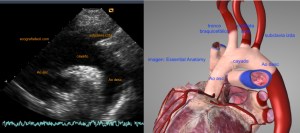

139. Ecocardiografía. Estudio Paraesternal Eje Largo.